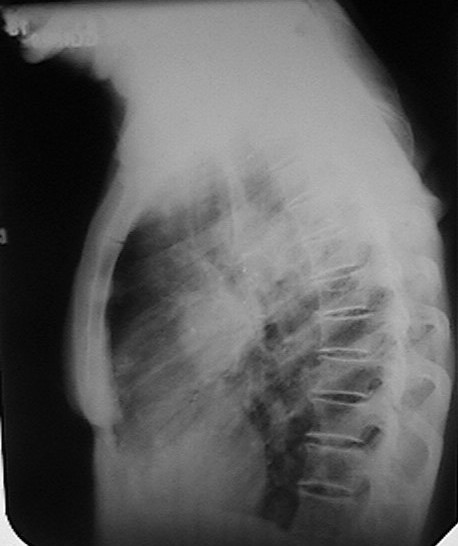

Fig. 19b.

Proyección

lateral izquierda

del caso anterior

donde se aprecia que la lesión ocupa un plano medio. Moderada artrosis. |